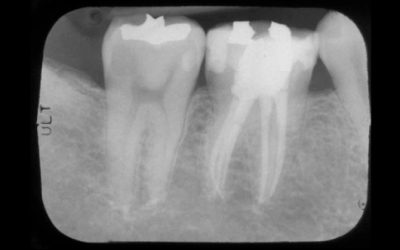

Tratamento de canal enfraquece o dente?

Ouvi dizer que tratamento de canal enfraquece o dente. É verdade? Quando um paciente é submetido a um tratamento de canal (endodontia) essa é a primeira pergunta que...